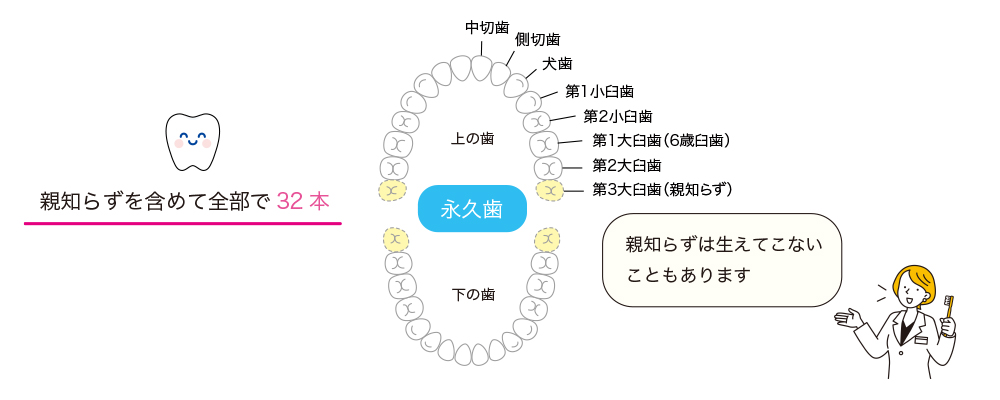

親知らずは「第3大臼歯」のこと

親知らずは、正式には「第3大臼歯」と呼ばれ、10代後半から20代前半にかけて生えてくることが多い歯です。成人後に親に知られずに生えてくる歯であることが、「親知らず」という名称の由来だと言われています。現代人は顎が小さくなっている傾向があり、親知らずがきれいにまっすぐ生えるスペースが足りないことが少なくありません。また、親知らずが1本も存在しない(先天欠如)人も日本人では10〜20%程度存在します。